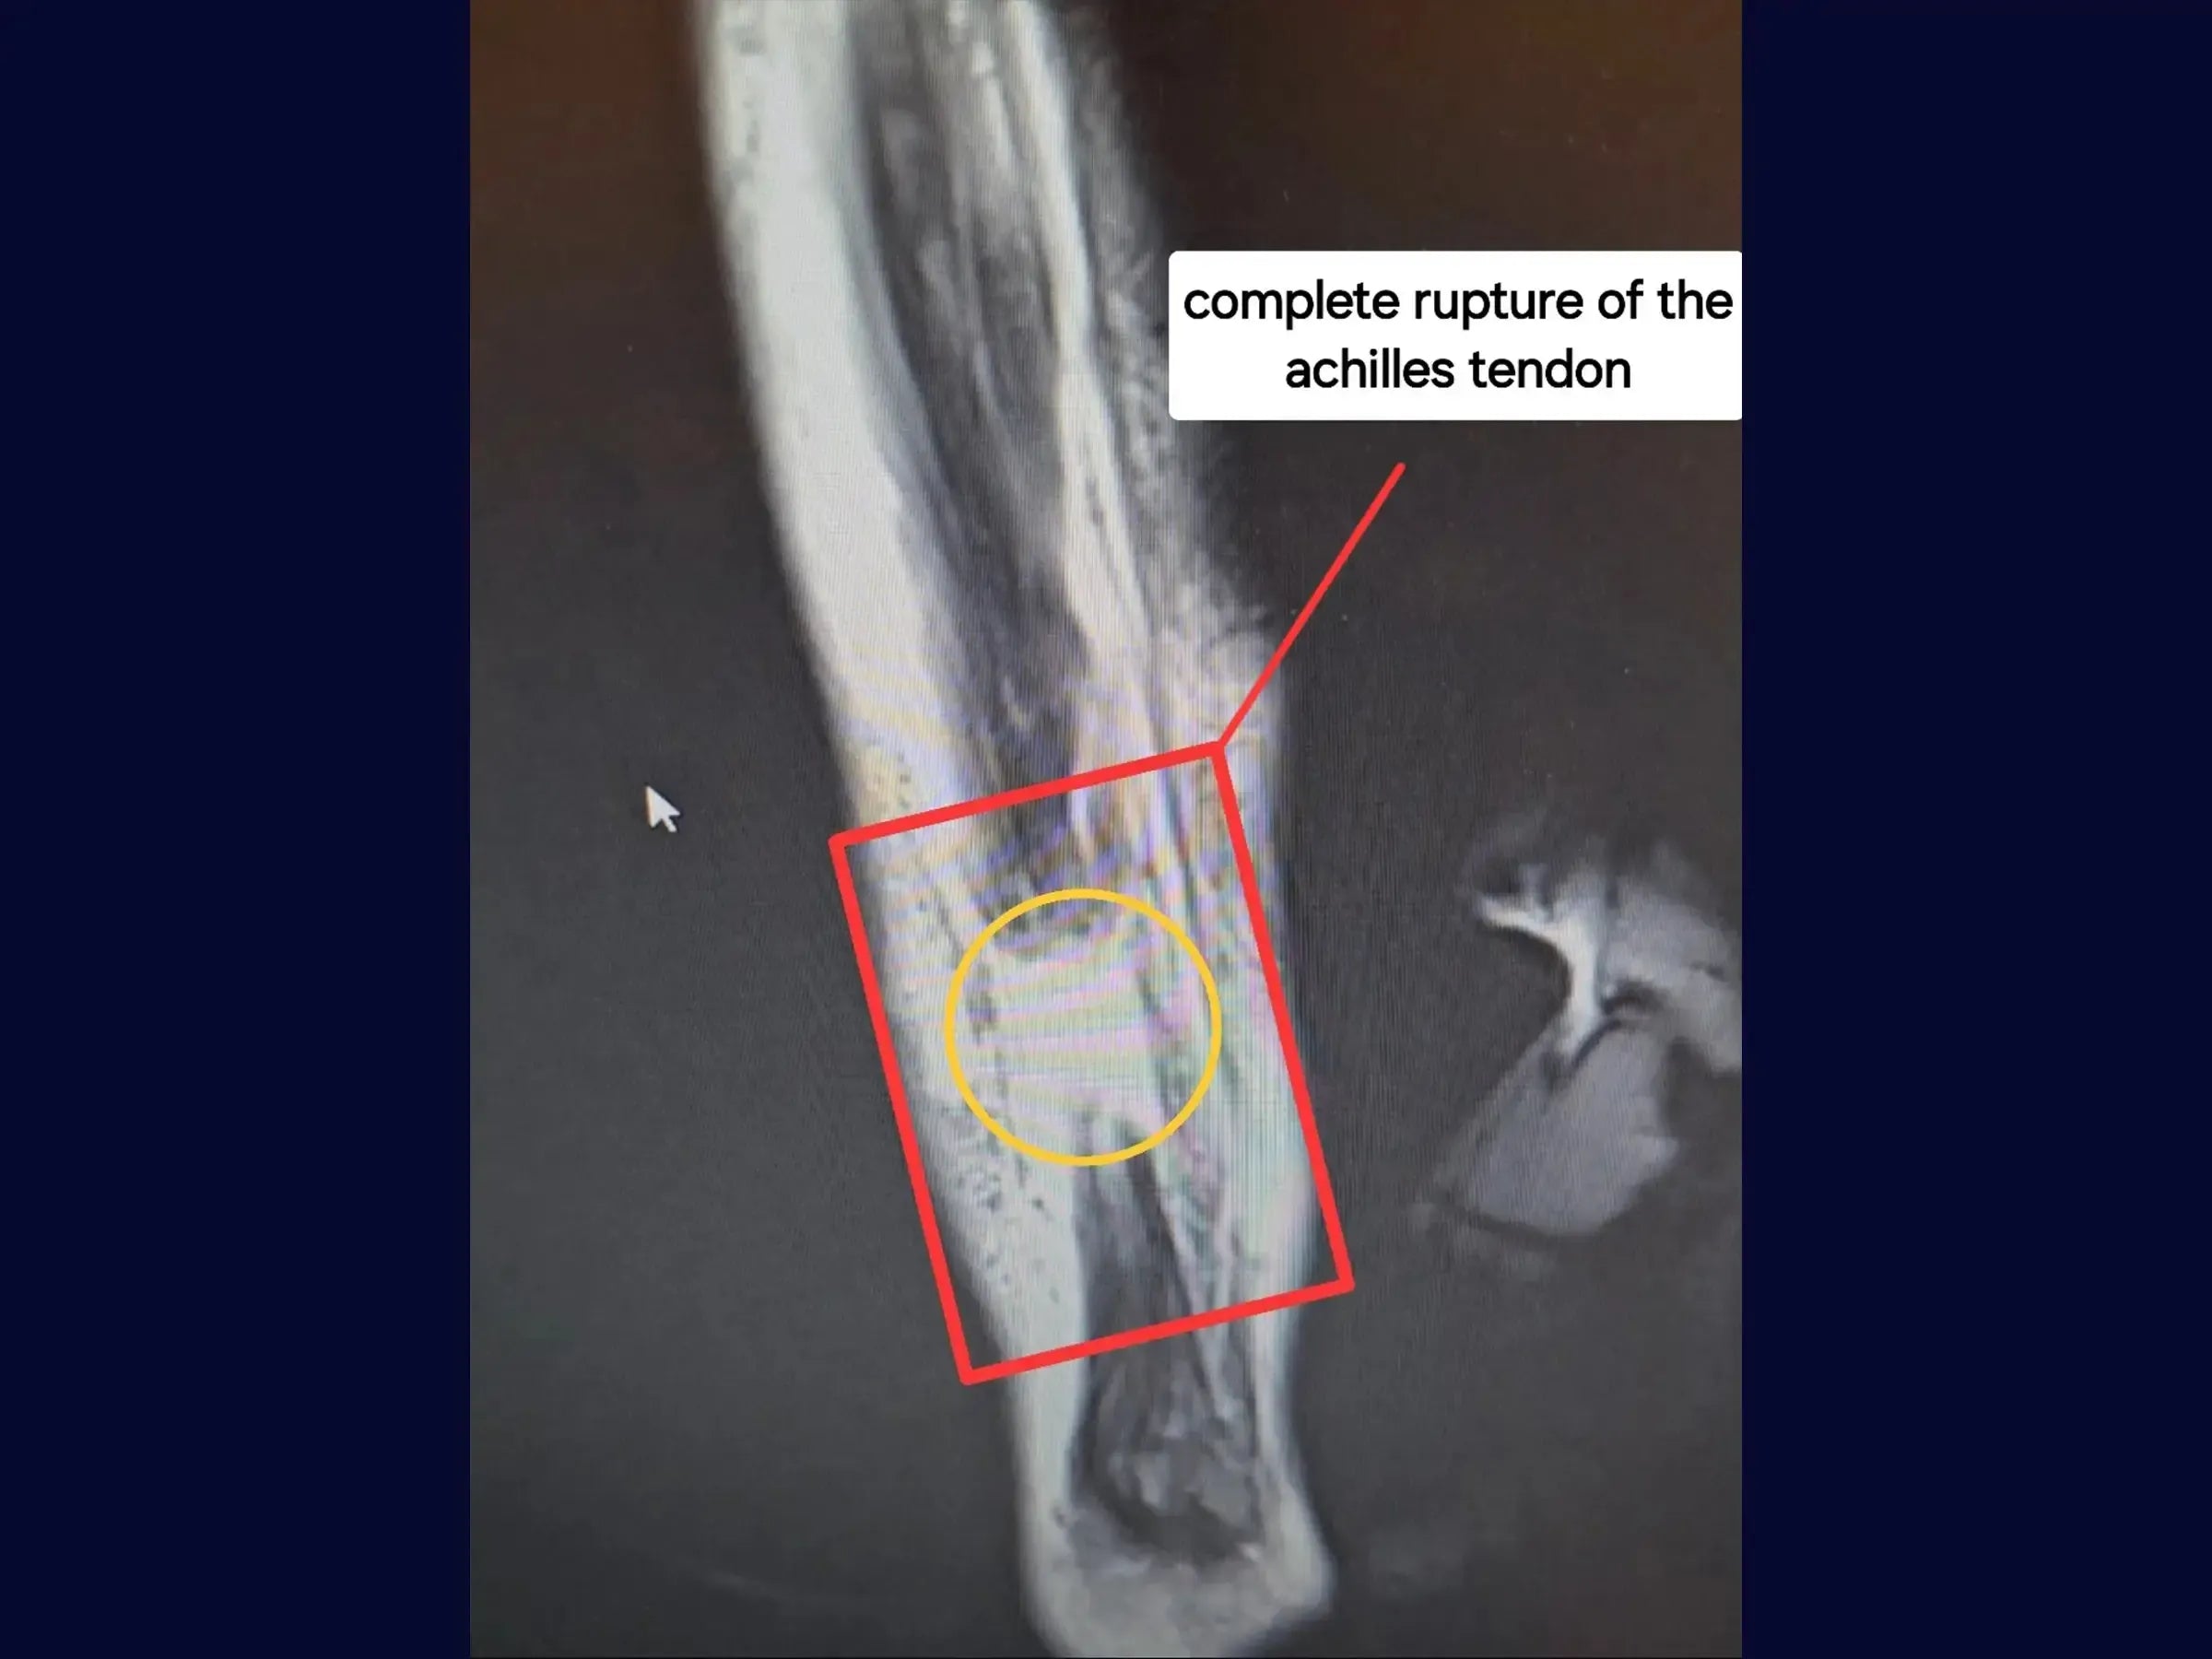

- Reparación Anatómica del Tendón de Aquiles: Técnica de osteosíntesis del tendón de Aquiles utilizando FiberTape y suturas de alta resistencia (punto Krackow) para estabilidad primaria.